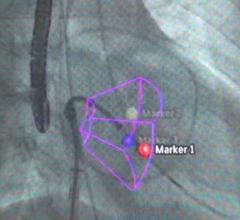

Hologic Inc. recently expanded its array of interventional and imaging solutions for breast health with the launch of the world's first 3-D breast biopsy option. This technology was developed for the company's Affirm upright breast biopsy guidance system, which is used in conjunction with the Selenia Dimensions 2-D and 3-D mammography systems.